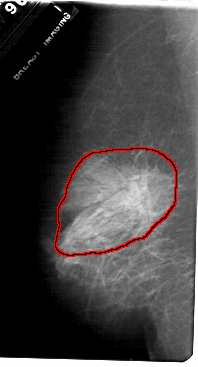

FILE: A_1720_1.RIGHT_CC.OVERLAY

TOTAL_ABNORMALITIES 1

ABNORMALITY 1

LESION_TYPE MASS SHAPE ARCHITECTURAL_DISTORTION MARGINS SPICULATED

ASSESSMENT 4

SUBTLETY 2

PATHOLOGY MALIGNANT

TOTAL_OUTLINES 1

BOUNDARY